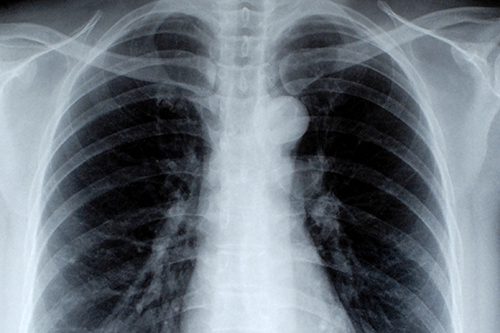

Nous sommes déterminés à sensibiliser nos adhérents aux différentes maladies respiratoires et à leur diffuser des informations utiles.

Notre engagement est de soutenir et accompagner les personnes atteintes de ces maladies, en leur offrant des ressources et des services adaptés à leurs besoins. Ensemble, nous travaillons pour améliorer la qualité de vie des personnes touchées par ces conditions respiratoires, en mettant l’accent sur l’empathie, l’entraide et l’accès à des informations fiables.